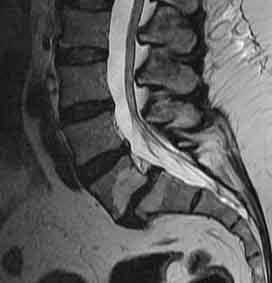

МРТ поясничного отдела позвоночника. Цветовая обработка Т2-взвешенного сагиттального МРТ. Норма.

МРТ поясничного отдела позвоночника. Сагиттальная и аксиальная Т2-взвешенные МРТ в норме.

На МРТ позвоночника дегенеративные изменения диска проявляются в виде уменьшения яркости от пульпозного ядра. Эта тенденция имеет отчётливую зависимость от возраста. Процесс начинается с задней части диска, затем распространяется на весь диск, граница пульпозного ядра и фиброзного кольца стирается. После 30 лет в пульпозном ядре появляется фиброзная ткань. Снижение высоты диска зависит не только от его дегенерации, но и нагрузки на диск. Остеохондроз часто сопровождается дегенеративными изменениями прилежащих к диску участков костного мозга тел позвонков и, иногда, корней их дуг.